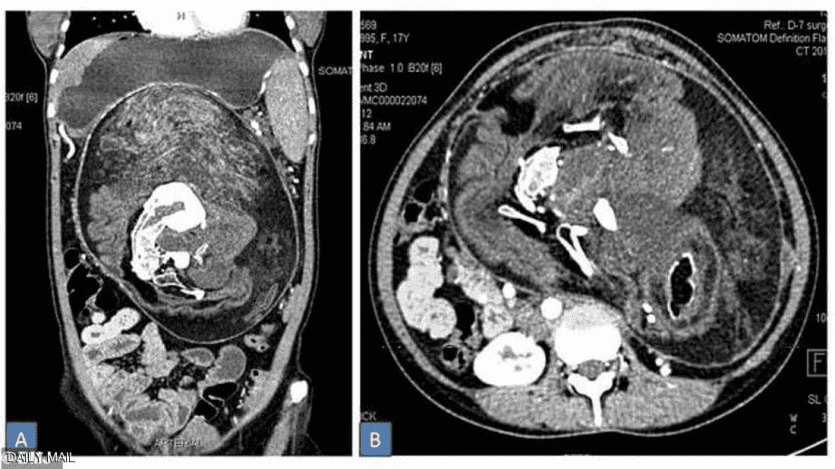

وبعد إجراء تصوير بالأشعة والتصوير المقطعي، اتضحت طبيعة الكتلة الغريبة داخل أحشاء الفتاة وتم التعرف عليها على أنها مجموعة كاملة من الأعضاء والأنسجة، وبدت بعض المناطق مثل الدهون، بينما ظهرت مناطق أخرى مثل الأنسجة الرخوة للأعضاء، ثم بعض الأجزاء الصلبة المكونة من الكالسيوم، والتي بدت بيضاء صارخة في التصوير بواسطة الأشعة المقطعية.

وعند الفحص الدقيق، تبين أن أجزاء الكالسيوم ما هي إلا عظام، وعلى وجه التحديد، فقرات وأضلاع وعظام طويلة.

كان ذلك قبل عامين، عندما قرر الأطباء إجراء عملية جراحية لإزالة هذه الكتلة، التي تبين أنها تحتوي بالفعل على العظام والشعر وعدة أسنان بالإضافة إلى "هياكل تشبه براعم الأطراف".